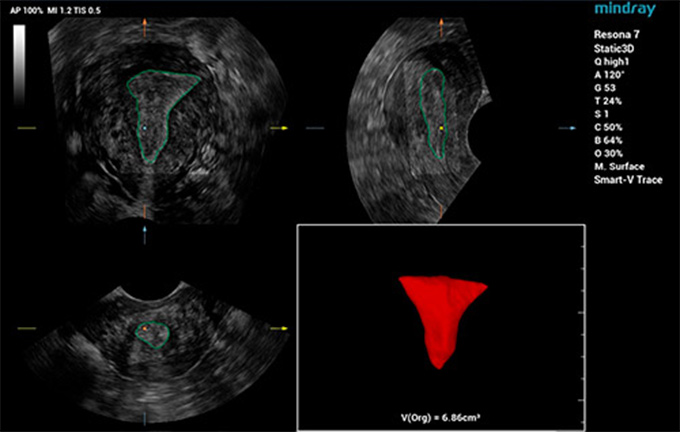

Eigen oplossingen voor de bekkenbodem

In het verleden is de kwestie van de bekkenbodemgezondheid van vrouwen na de bevalling niet voldoende onder de aandacht gebracht. Veel mensen denken zelfs ten onrechte dat bekkenbodemaandoeningen, zoals orgaanverzakking, urine-incontinentie en bekkenpijn 'normale' ziektebeelden zijn na een bevalling of bij het ouder worden. Echografisch onderzoek helpt de gezondheid van de vrouwelijke bekkenbodem te herkennen en nauwkeurig te beoordelen.

De beoordeling van de plaats en de morfologie van alle bekkenweefselstructuren en de levator hiatus staan centraal bij echografisch bekkenbodemonderzoek. De traditionele handmatige bediening is echter zowel tijdrovend als afhankelijk van de operator en onervaren echografisten hebben vaak problemen met de lokalisatie. Ondertussen kan het ineffici?nte scanproces de gêne en het ongemak van de pati?nt verdubbelen. Met de toenemende bewustwording van de bekkenbodemgezondheid van vrouwen is te voorzien dat er een groeiende vraag is naar echografisch bekkenbodemonderzoek. Daarom is het absoluut noodzakelijk om een nauwkeurigere, effici?ntere en gebruiksvriendelijkere diagnostische methode voor bekkenbodemechografie te ontwikkelen.

Om echografisten te helpen snel gestandaardiseerde secties en metingen te verkrijgen bij complexe bekkenbodemonderzoeken en de diagnostische effici?ntie te verbeteren, heeft Mindray Smart Pelvic ontwikkeld, een slimme oplossing voor echografie van de bekkenbodem. Deze oplossing kan automatisch volledige bekkenmetingen verrichten en automatische 3D-beeldvorming bieden van de levator hiatus, samen met metingen van de longitudinale diameter, de transversale diameter, het levator hiatus-gebied, en de grootte van de urethra-opening van de levator. Echografisten kunnen uitgebreide klinische gegevens krijgen voor een nauwkeurige beoordeling via een paar eenvoudige interacties, die slechts een derde van de tijd van traditionele onderzoeken in beslag nemen. Daarnaast biedt Mindray drie primaire industri?le standaarden die verschillende soorten sondes ondersteunen en een gestandaardiseerde werking mogelijk maken.

Smart Pelvic